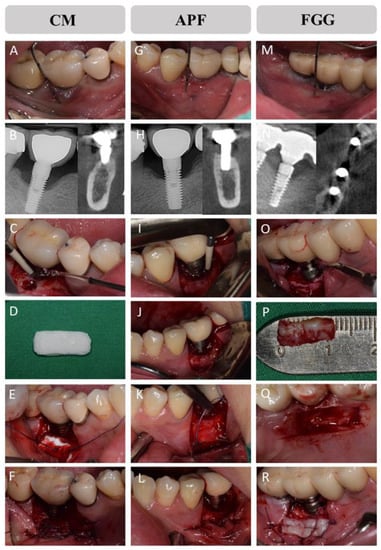

2.3. Allocation and Surgical Procedures